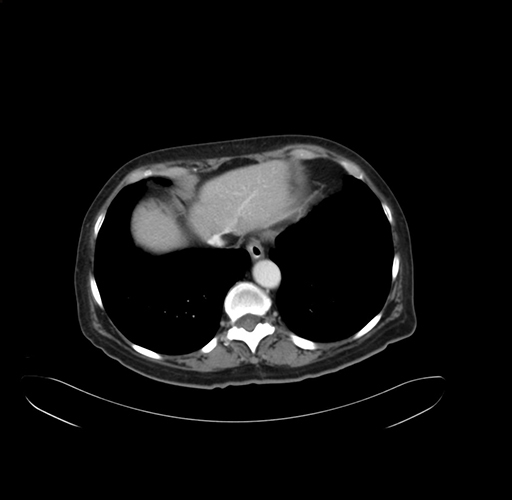

Pre-Chemo: Axial Venous

Axial Venous